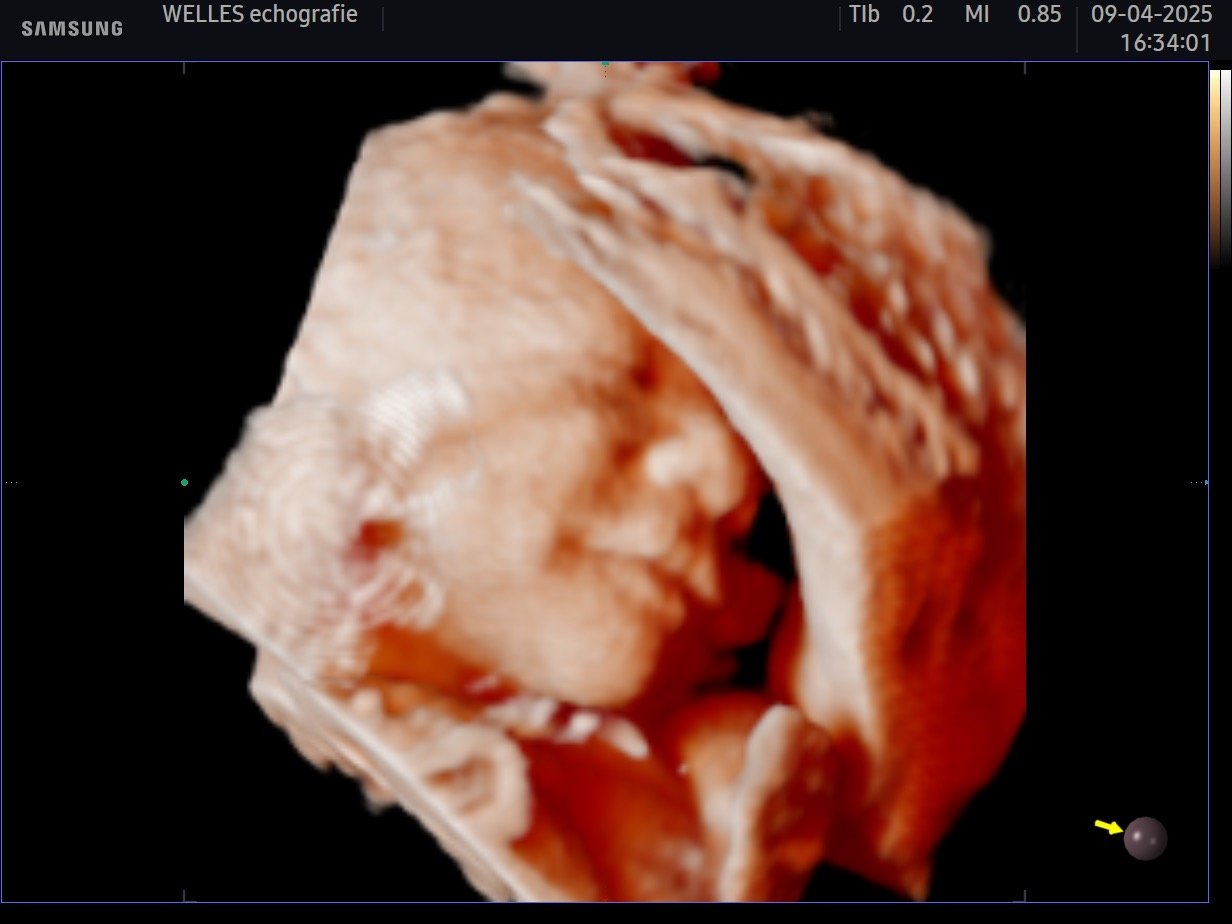

De pretecho wordt gemaakt met moderne apparatuur voorzien van de nieuwste updates. Toch kan het zijn dat de beelden niet helemaal uitpakken zoals je hoopt. Dit is afhankelijk van een aantal factoren, zoals de ligging van je placenta, de hoeveelheid vruchtwater en de voorkeurshouding van je kindje.

(Van toepassing bij een reguliere pretecho in de optimale zwangerschapstermijn van 24-30 weken.)

3D echo 4D pretecho